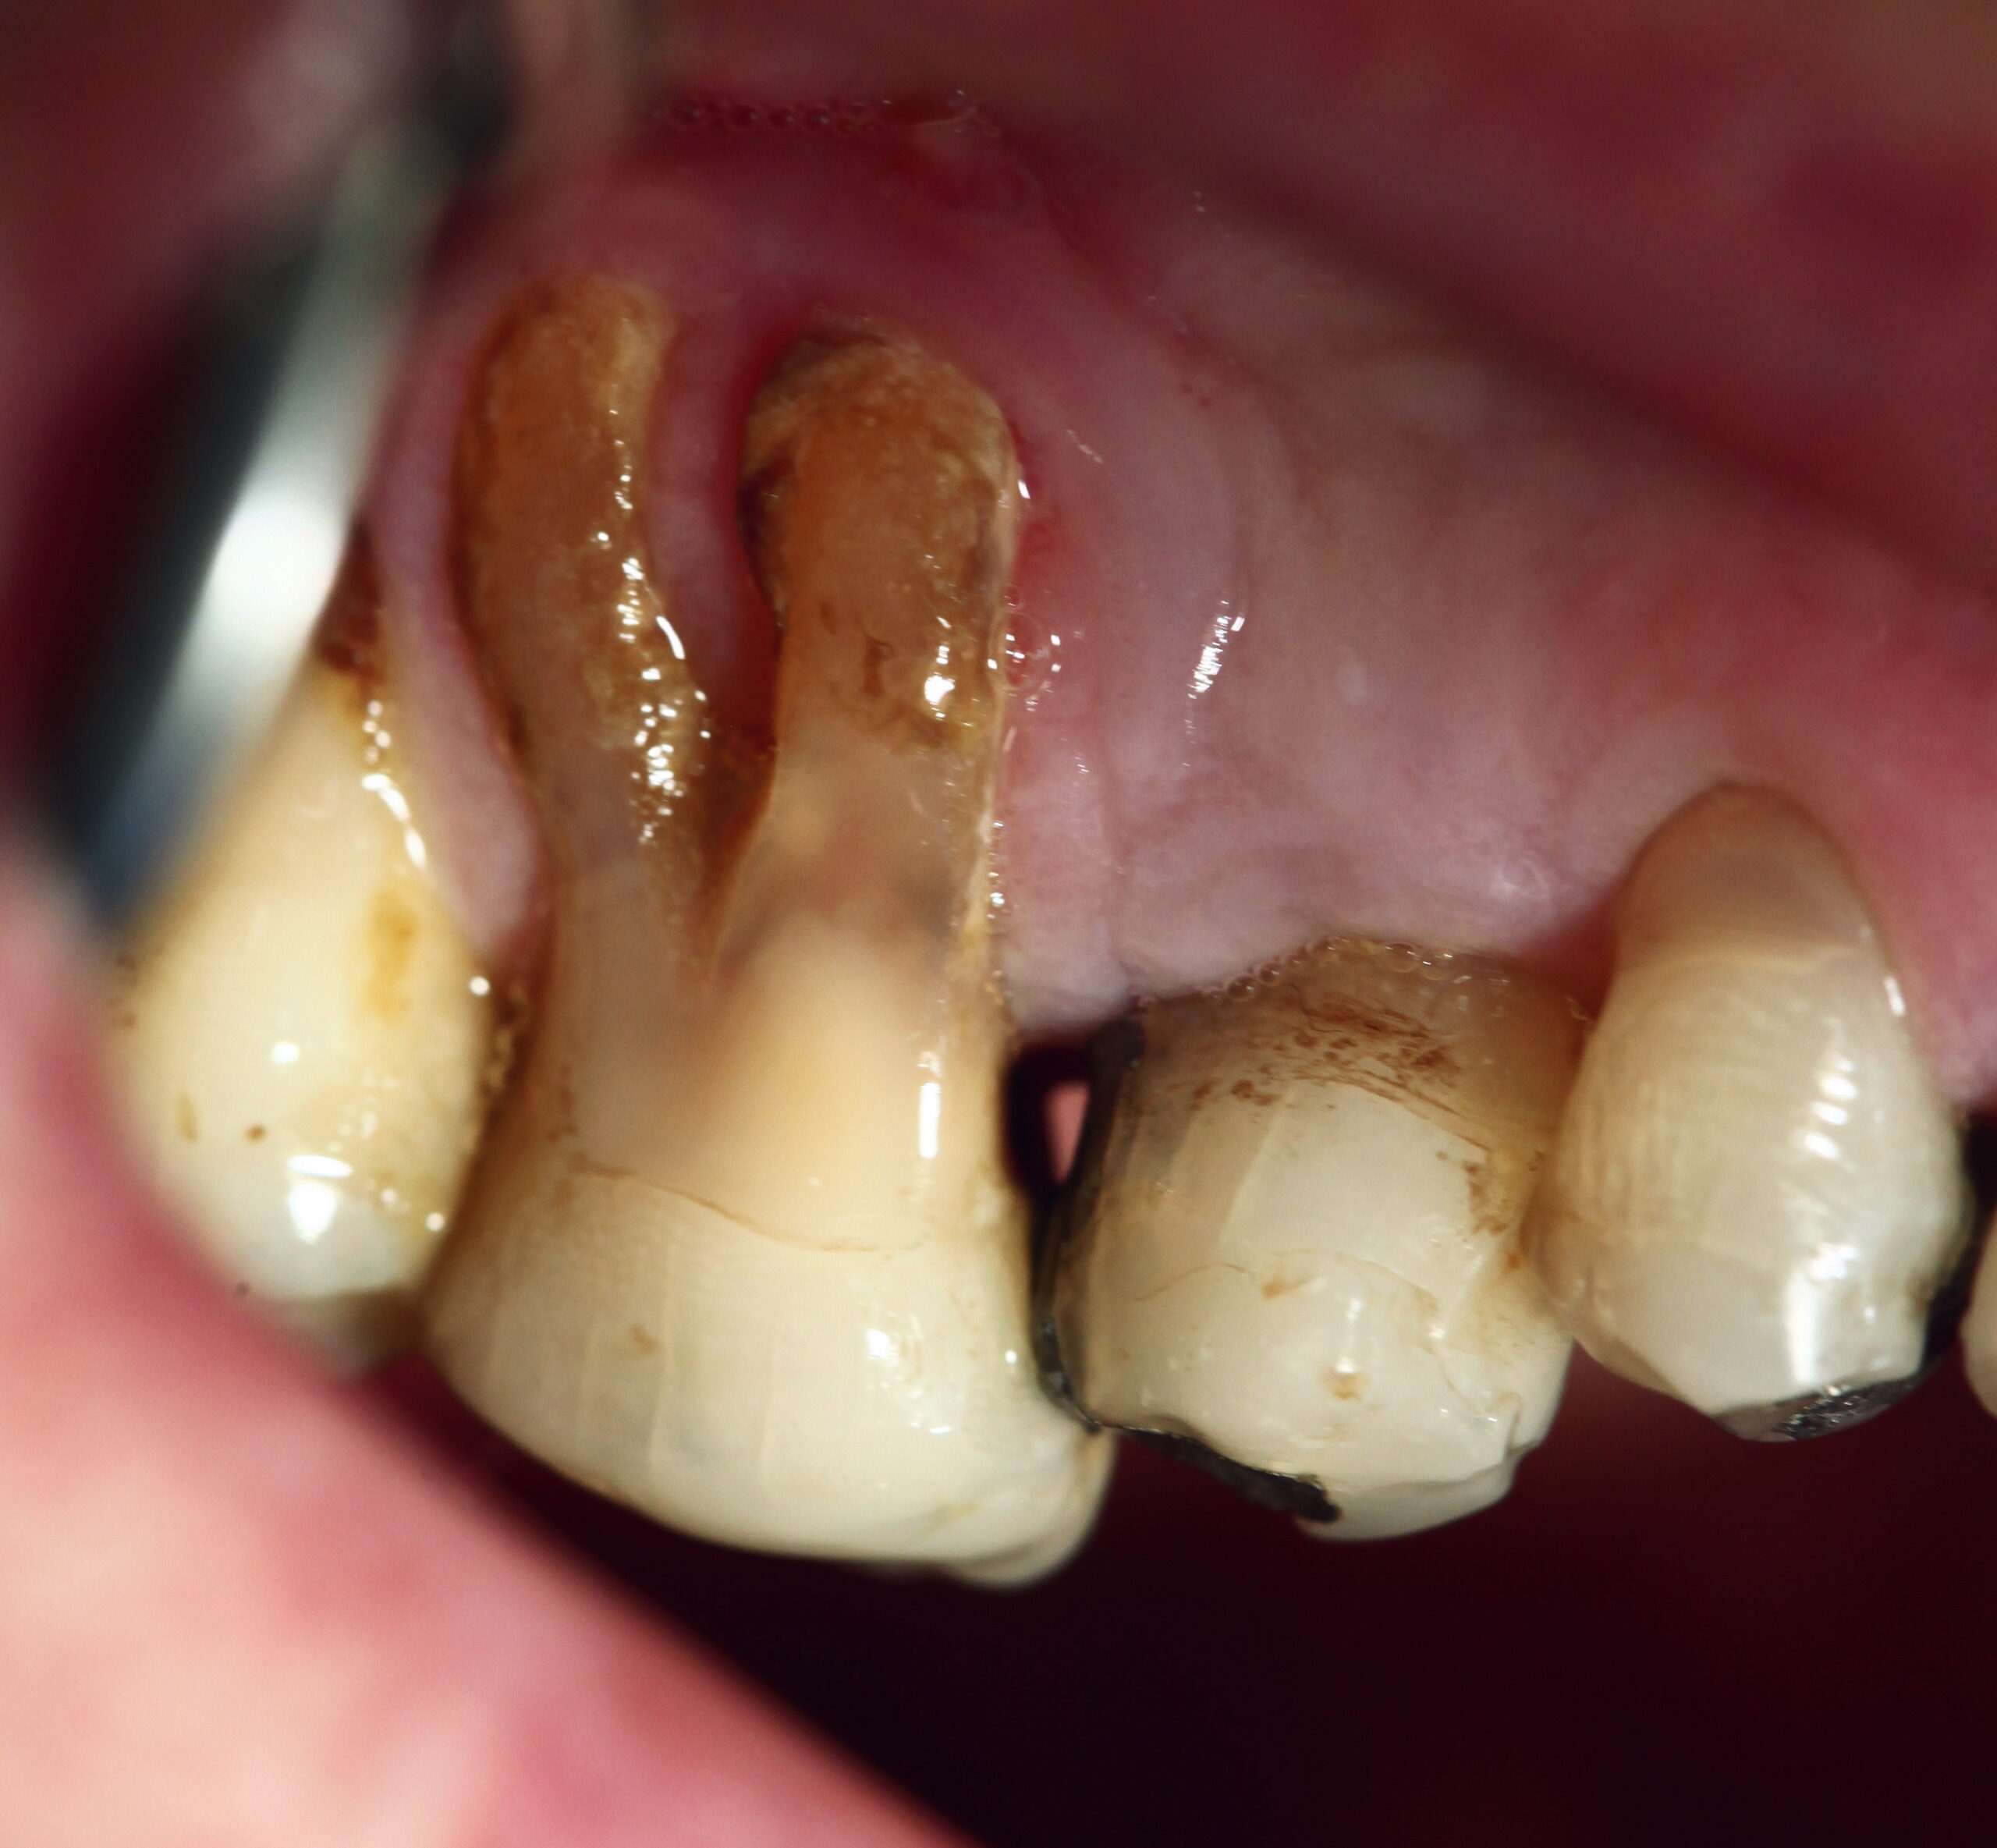

- Отдръпващи се от зъбите венци, което прави зъбите да изглеждат по-дълги от нормалното.

В случаите, когато възпалението е продължително във времето, нелекувано и превърнало се в хронично, се стига до появата на пародонтит. А при него има образуване на дълбоки джобове между венците и зъбите, които джобове се пълнят с плака, зъбен камък и бактерии и с течение на времето стават все по-дълбоки. Ако не се лекуват, този тип инфекции причиняват загуба на венечна и костна тъкан. В крайна сметка човек започва да губи и цели зъби. И сякаш това не стига, ами подобно дългогодишно възпаление може да натовари имунната система и да причини редица други здравословни проблеми.